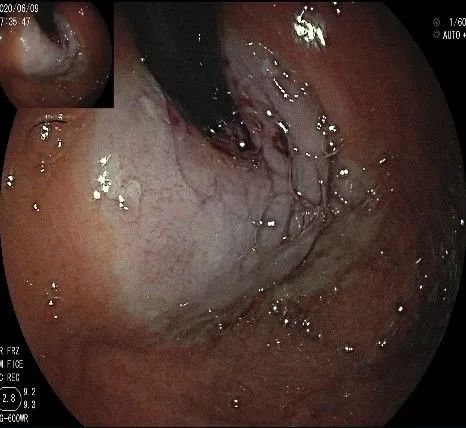

倒镜观察,可见贲门部一个明显的隆起,中央部分的凹陷,是4天前取活检留下的。

我们的思路:病变长径约2.0cm,位置活动,倒镜后先在胃底侧粘膜下注射,使病变向食管腔方向抬举,然后再在食管腔内做粘膜下注射切开,以获得一个好的术野,果然,注射后粘膜抬举明显,瘤体被挤向口侧。

正镜观察,瘤体就在贲门部齿状线的下方。